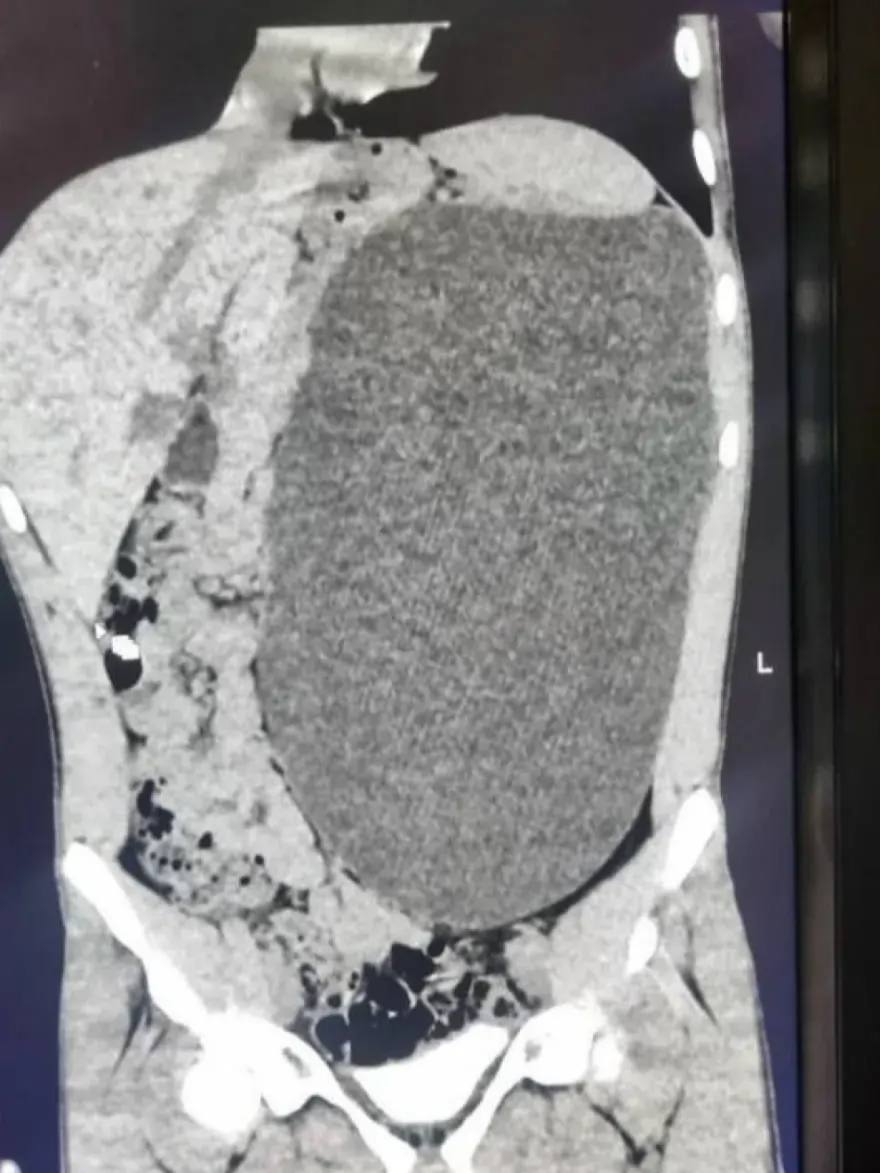

У юного сибиряка обнаружили почку с пятилитровую банку — орган занял чуть ли не весь живот и сдавил другие органы

Врачи нашли патологию случайно и назвали её «бомбой замедленного действия»: случайный удар по животу мог привести к разрыву этого образования.

В течение четырёх дней хирурги откачивали скопившуюся жидкость, а затем удалили поражённую почку. Подросток уже идет на поправку